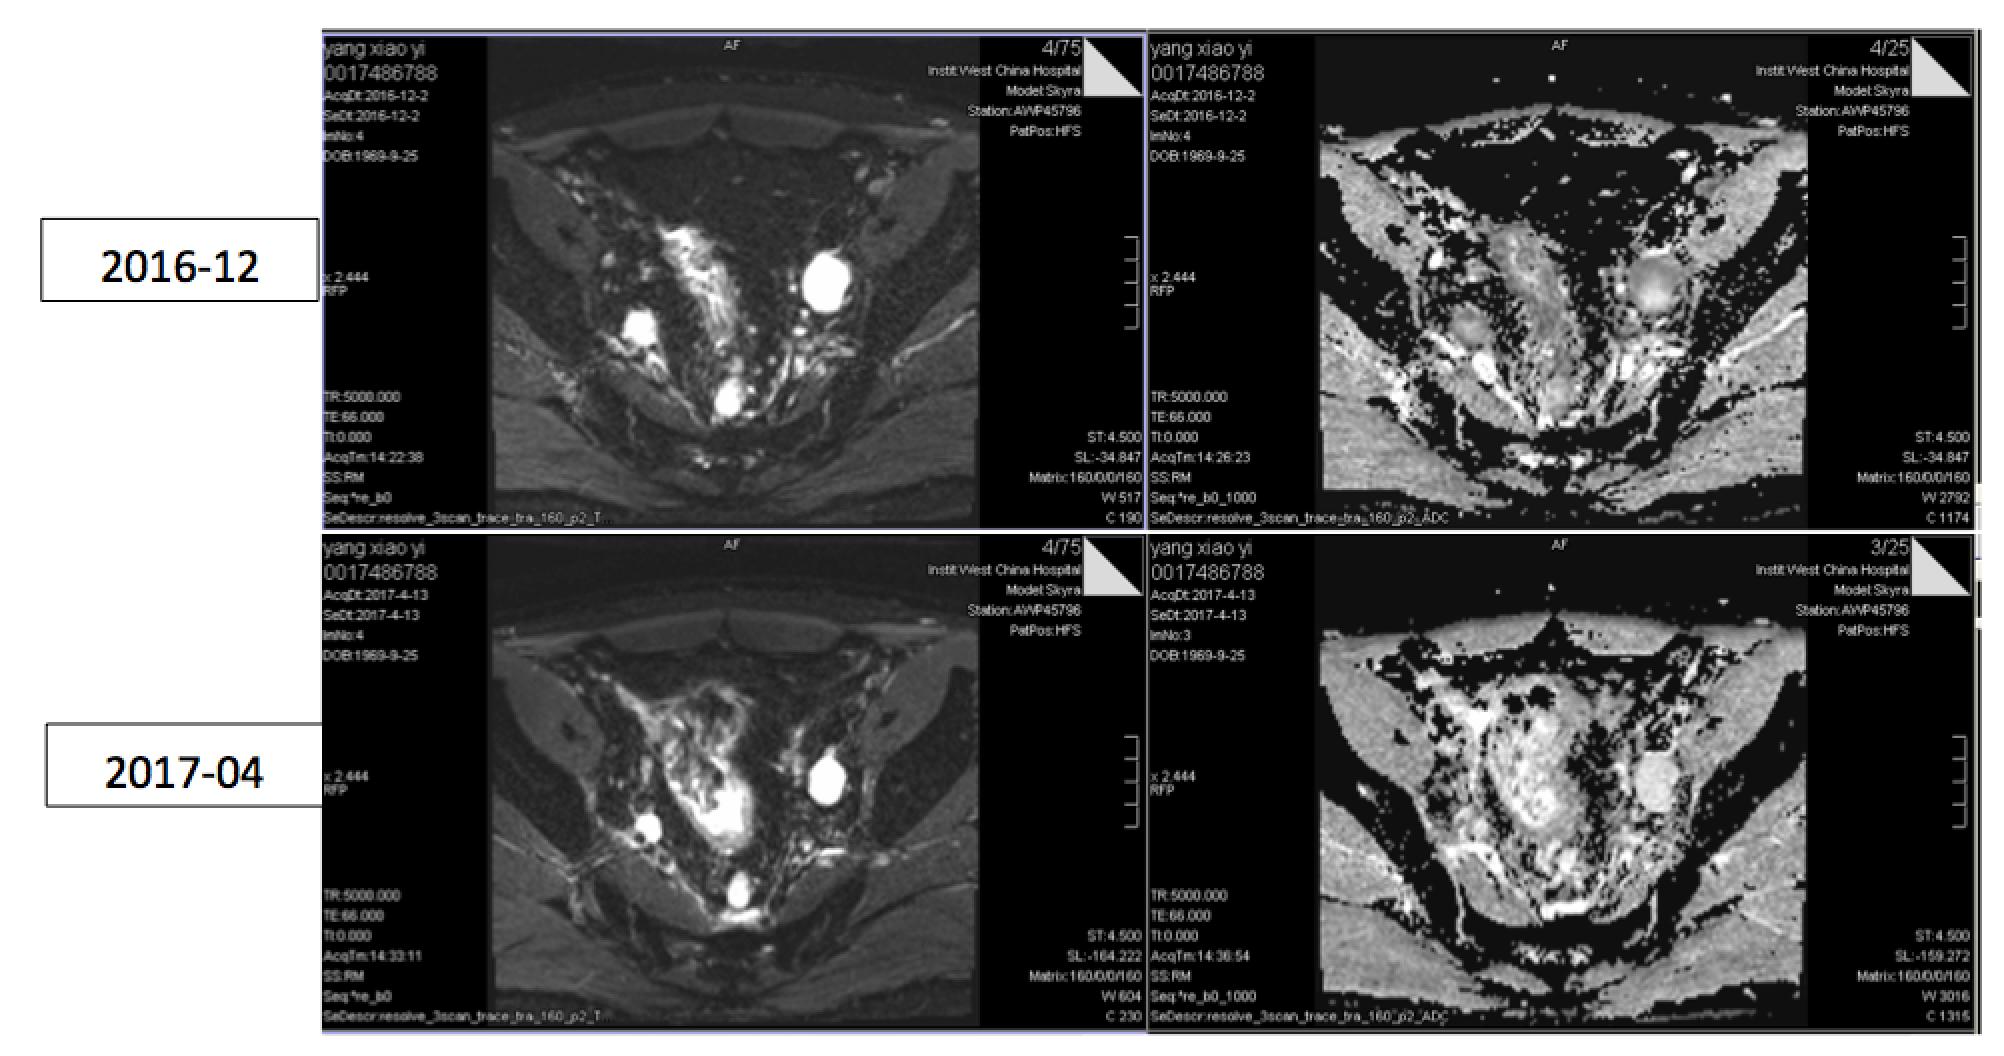

DWI

疗效评估(同步放化疗结束时,2017.2.14):SD

疗效评估(2017.4.26):PR?

N(淋巴结):直肠系膜区及盆腔多发增大淋巴结,DWI呈高信号,T2WI呈高信号,最大位于左侧髂血管旁,直径约4.0cm。

N(淋巴结):直肠系膜区及盆腔多发增大淋巴结,DWI呈高信号,T2WI呈高信号,最大位于左侧髂血管旁,直径约2.7cm。